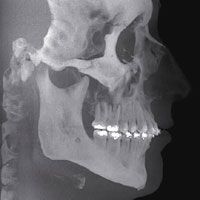

Diagnose von Erkrankungen

Mit hoher Genauigkeit können Verformungen an Knochen und

Kiefer vermessen werden. Knochenläsionen und Veränderungen

am Kiefer können beurteilt werden. Veränderungen wie

z. B. Zysten, Tumore und Krankheiten werden dargestellt und erkannt.

Kiefergelenkerkrankungen

Mit dreidimensionalen Bildern werden das Kiefergelenk und

die umgebenden Strukturen dargestellt. Damit kann die Aufbau

des Kiefergelenks, der Kiefergelenkspalt und die Gelenkfunktion

vollständig analysiert werden – alle für die

Behandlung und Nachsorge wichtigen Parameter der Kiefergelenkerkrankung.